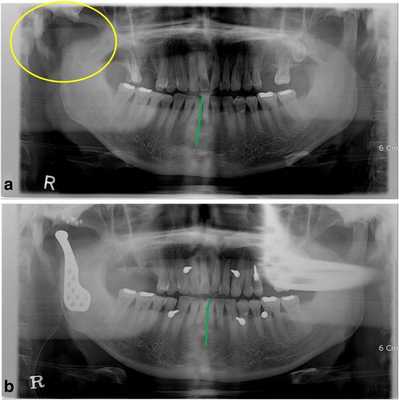

52-летний мужчина обратился за помощью по причине нарушения прикуса после кондилэктомии. Он упал вниз по лестнице и сломал нижнюю челюсть в области шейки суставного отростка. В больнице ему провели открытую редукцию поврежденной области с фиксацией частей сустава. После операции произошло инфицирование области правого ВНЧС, из-за чего пришлось провести удаление суставного отростка. Через месяц после оперативного вмешательства он обратился за помощью в стоматологическую клинику Университета Йонсей. В состояние покоя его нижняя челюсть была смещена вправо, а окклюзионное соотношение челюстей было нарушено вследствие кондилэктомии (фото 1а).

Фото 1.

а) Смещение нижней челюсти вправо (зеленая линия) в результате кондилэктомии (желтый круг).

b) Панорамная рентгенограмма, полученная через 1 день после операции, продемонстрировала восстановление окклюзионного соотношения (зеленая линия). Для стабилизации окклюзии во время операции были использованы межчелюстные фиксационные винты.

Диапазон раскрытия рта был ограничен расстоянием в 30 мм. После назначения пероральных антибиотиков с целью обеспечения инфекционного контроля была запланирована операция по реконструкции правого ВНЧС с использованием суставного протеза. Во время операции хирурги обеспечивали стабилизацию окклюзии путем межчелюстной фиксации для восстановления первоначального соотношения верхней и нижней челюстей. Установку суставного протеза проводили через два разреза: один - в околоушной области, другой - в подчелюстной по Risdon. Панорамная рентгенограмма, полученная через день после операции, подтвердила восстановление нормального окклюзионного соотношения (фото 1b). Через 3 дня пациента выписали без каких-либо осложнений послеоперационных осложнений, обеспечивая наблюдение на протяжении одного года. Протез функционировал достаточно хорошо, а восстановленная окклюзия оставалась стабильной, хотя максимальное открытие полости рта так и не удалось увеличить более чем до 30 мм.